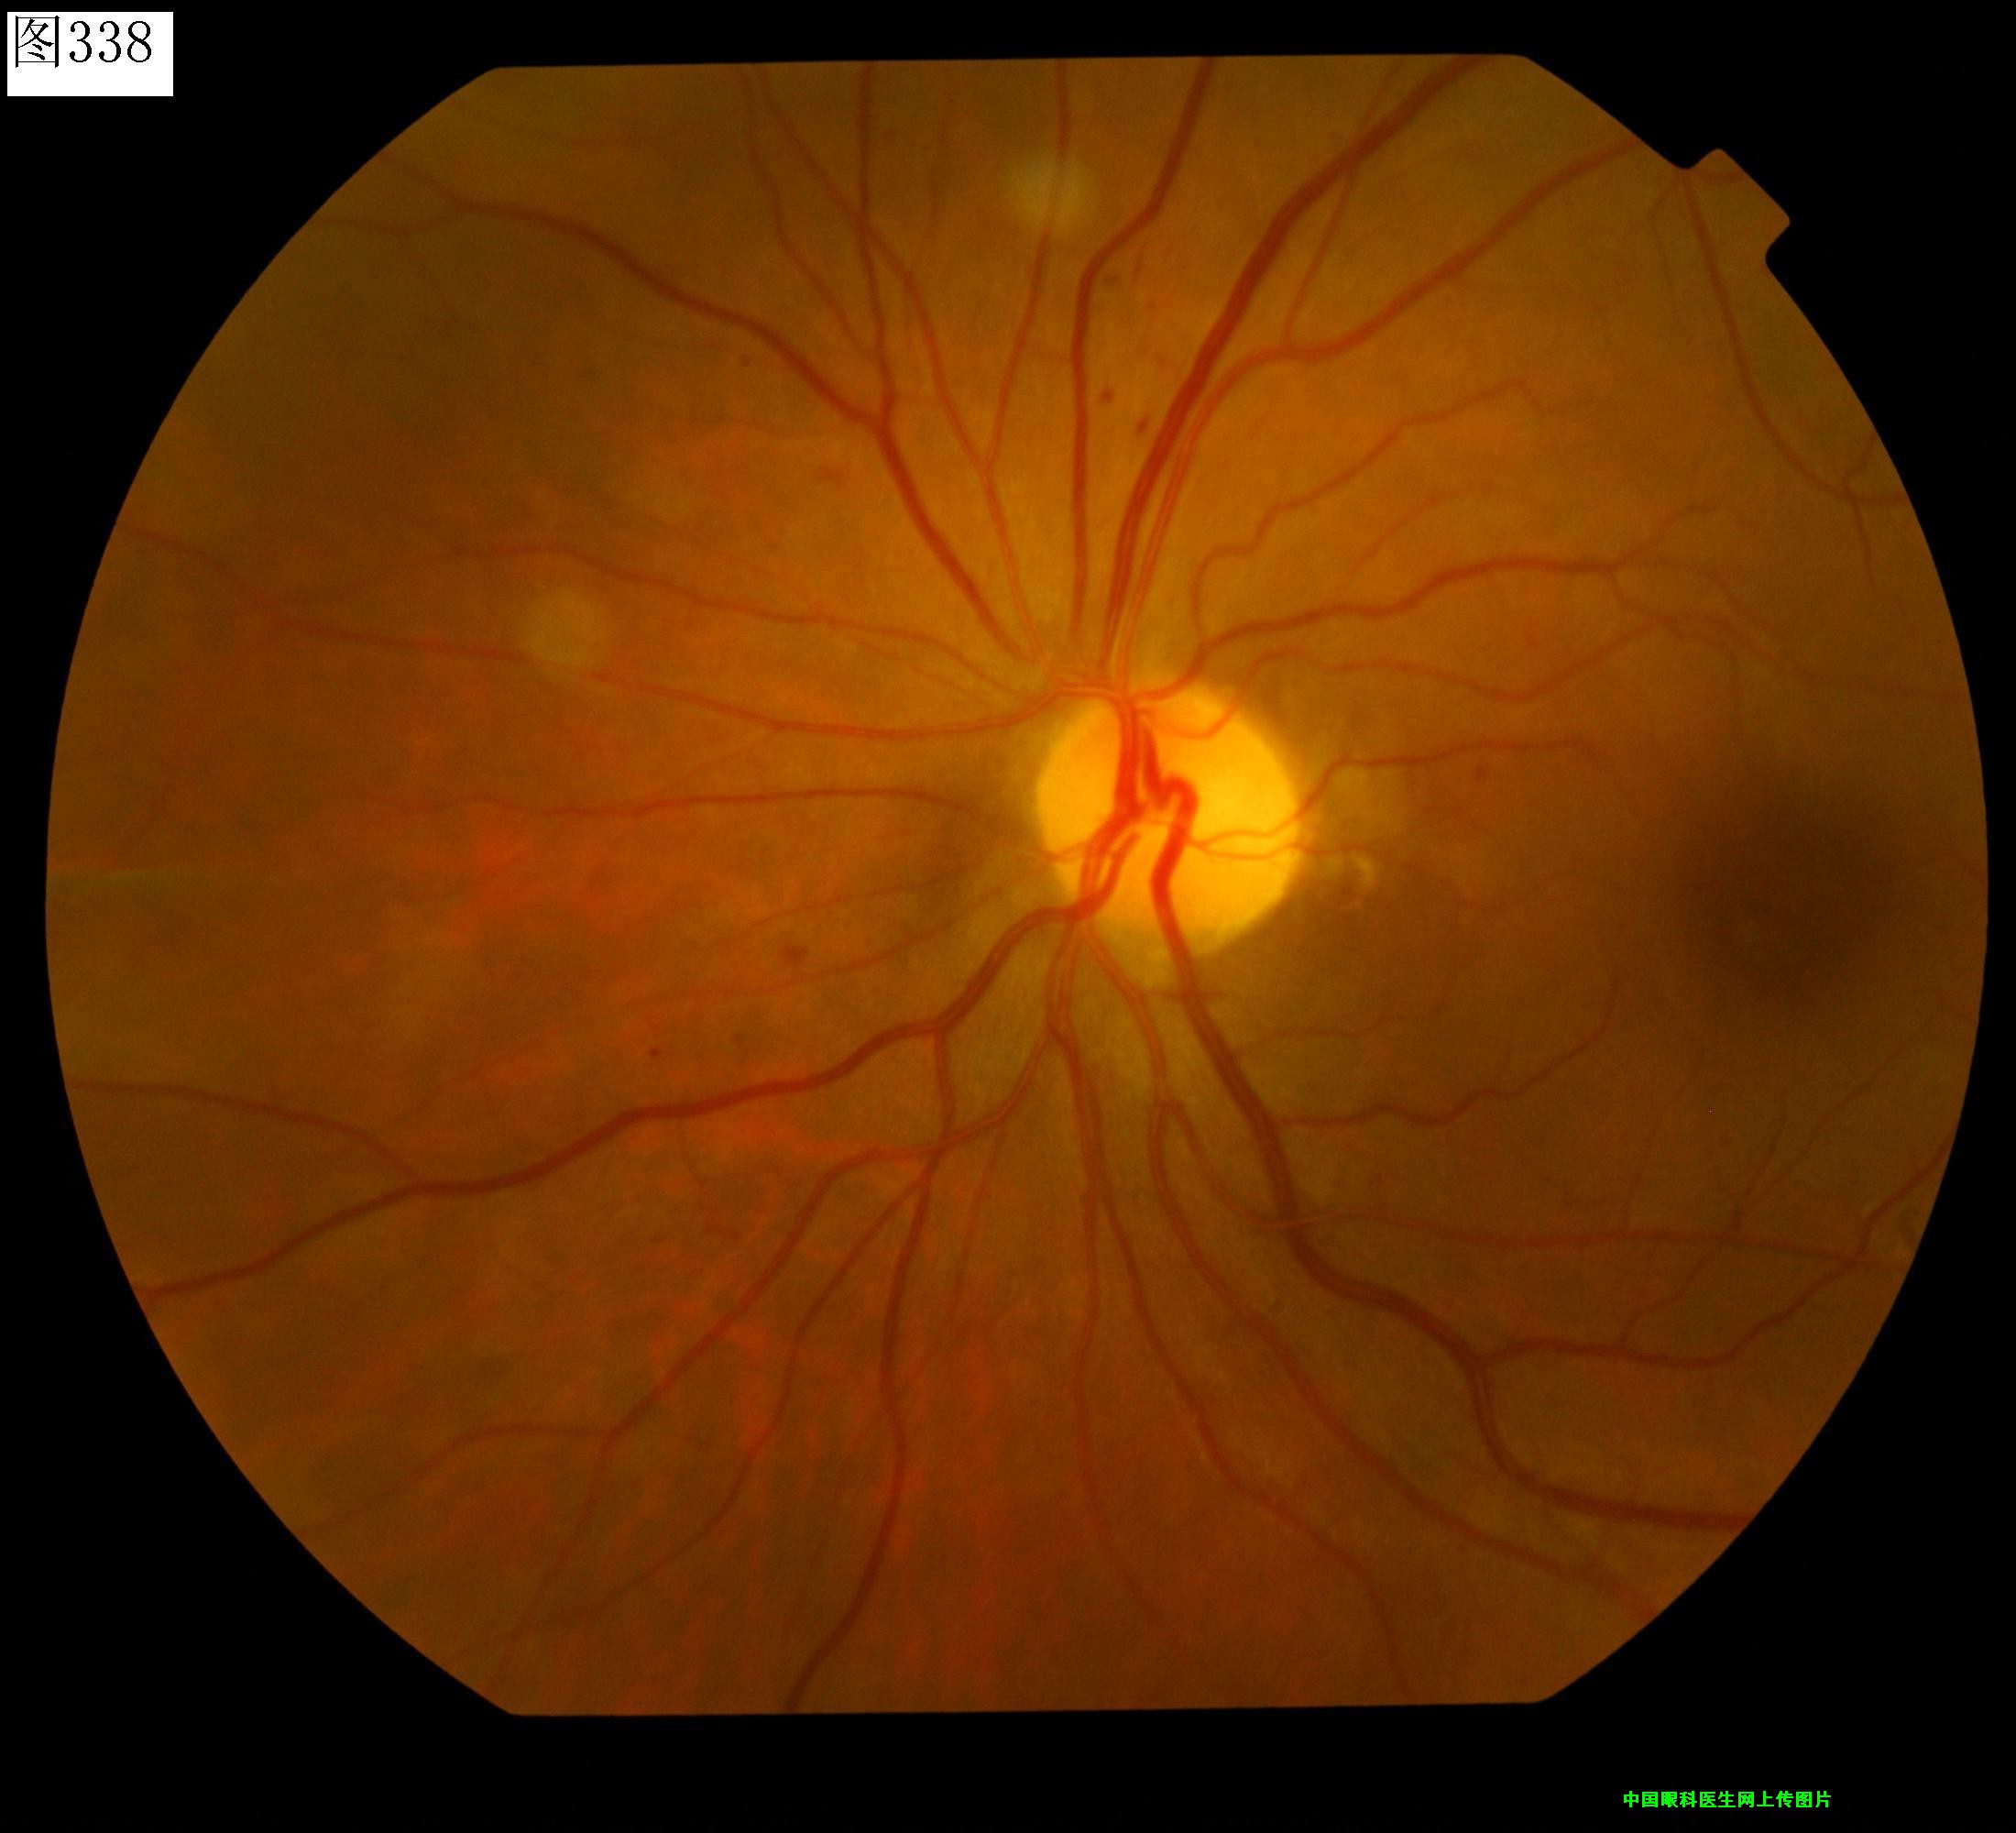

337 338 339 340